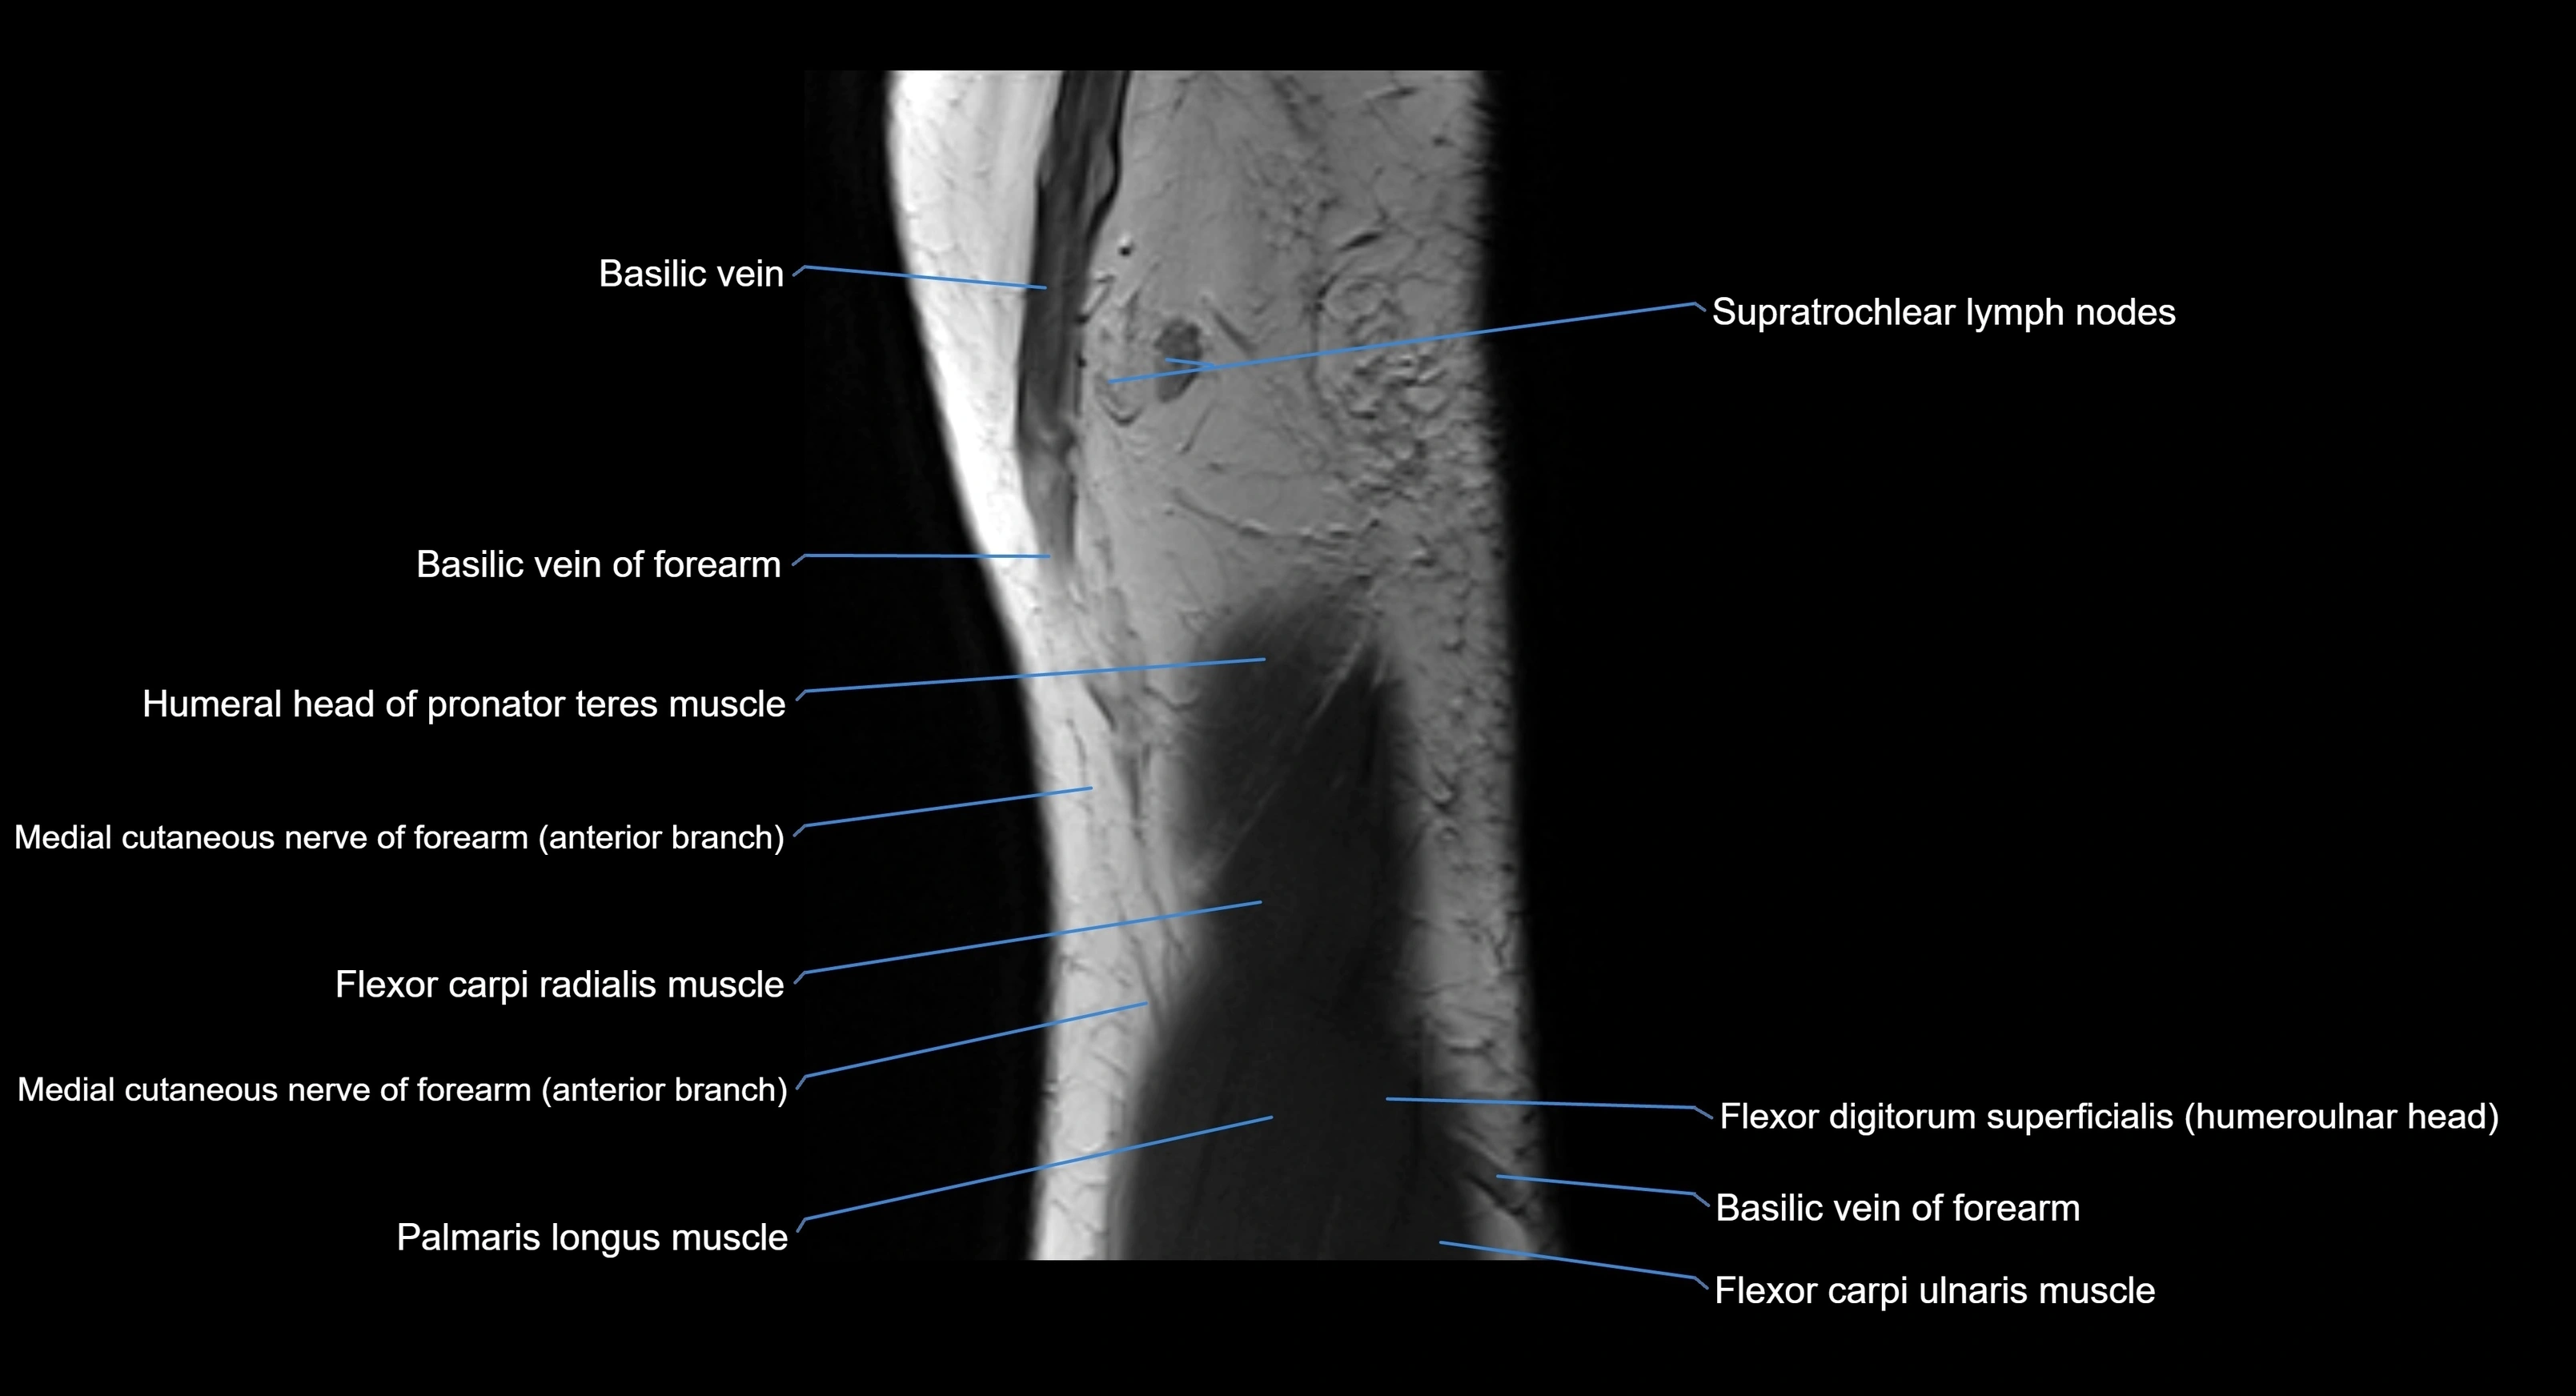

MRI image

image